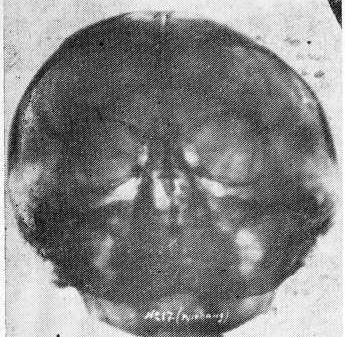

Рис. 3. Фотокопия рентгенограммы черепа в подбородочно-носовой проекции больной Б., 24 лет (диагноз — злокачественная шизофрения, состояние дефекта). На снимке определяется метопический шов, кости свода истончены.

Рис. 4. Фотокопия с подбородочно-носовой рентгенограммы черепа матери больной Б. (рис. 3) в возрасте 45 лет (имеет шизоидные особенности характера). На снимке: так же, как и у дочери, определяется незаращенный метопический шов, правая верхнечелюстная пазуха в два раза меньше в размерах, чем левая.